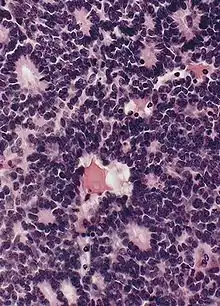

Псевдорозетки Гомера Райта является одним из видов псевдорозеток, в котором дифференцированные клетки опухолей окружают нейропиль.[7] Примерами опухолей, содержащих эти розетки, являются нейробластома, медуллобластома, пинеалобластома и примитивные нейроэктодермальные опухоли кости. Розетки Гомера Райта являются «псевдо» в том смысле, что они не настоящие розетки. Настоящие розетки — это розетки Флекснера-Винтерштайнера, которые содержат пустой просвет. Розетки Гомера-Райта содержат большое количество фибриллярного материала. Они названы в честь Джеймса Гомера Райта.

Микроскопический вид типичной нейробластомы с образованием розеток

Гистопатологический образец нейробластомы с розетками Гомера Райта, окраска гематоксилин-эозин